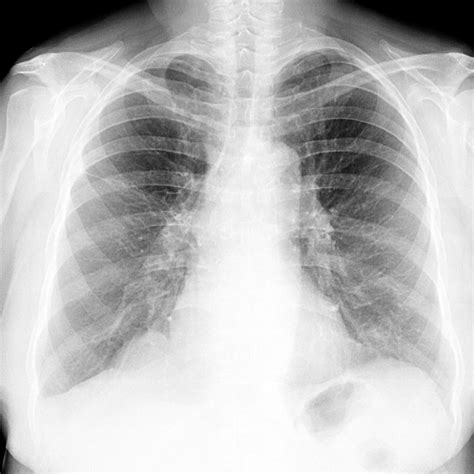

Emphysema is a chronic lung disease that affects millions of people worldwide. It is characterized by the destruction of the alveoli, the tiny air sacs in the lungs, leading to shortness of breath and other respiratory issues. One of the most pressing concerns for individuals diagnosed with emphysema is understanding their emphysema life expectancy. This post aims to provide a comprehensive overview of emphysema, its impact on life expectancy, and factors that can influence the progression of the disease.

Emphysema is a type of chronic obstructive pulmonary disease (COPD) that primarily affects the lungs. It is often caused by long-term exposure to irritating gases or particulate matter, most commonly from cigarette smoke. The disease leads to the breakdown of the alveoli, which are responsible for exchanging oxygen and carbon dioxide in the lungs. As a result, individuals with emphysema experience difficulty breathing, especially during physical exertion.

The severity of emphysema is often classified into stages based on the Global Initiative for Chronic Obstructive Lung Disease (GOLD) criteria. The stages range from mild to very severe, and the emphysema life expectancy generally decreases as the disease progresses.